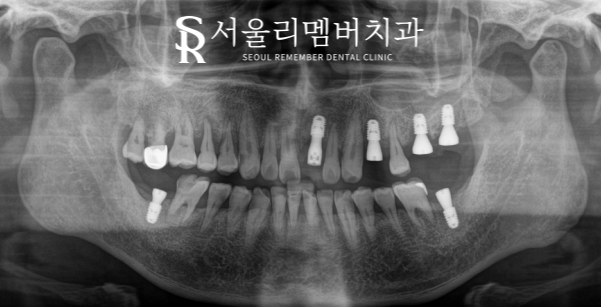

실제 환자분의 파노라마 사진을 보며 함께 설명드리도록 하겠습니다^^

서울대입구역치과 에서 오늘 보여드릴 환자분의 파노라마를 보면

아래 어금니 다수의 상실 및 심한 충치, 상악 소구치 상실이

구강 내에 나타나 있는 것을 볼 수 있었습니다.

이 중에서 특히나 오른쪽 상악 어금니를 살펴보면

심한 충치 및 염증으로 인해 치조골 소실이 나타나 있었는데요.

바로 이런 경우에 골이식이 필요한 것이죠!

파노라마에서 확인할 수 있듯이 하얗게 채워진 이식재가 관찰되네요.